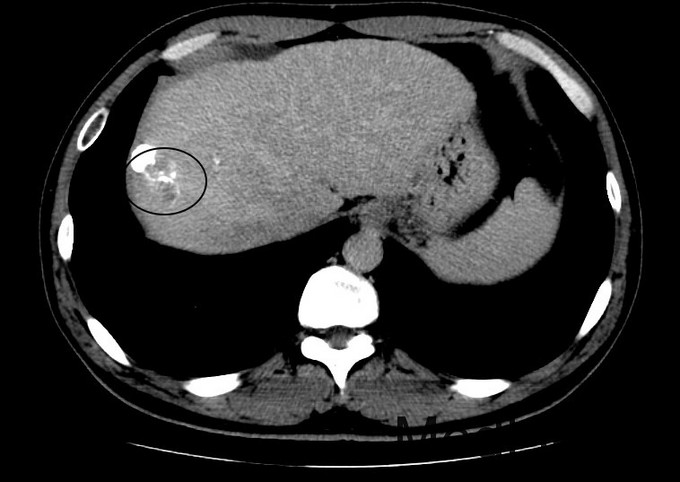

查体:血压131/76mmHg.神志清晰。颜色正常,无皮疹及瘀点。无肝掌。浅表淋巴结未触及肿大。眼睑无水肿,巩膜无黄染,结膜正常。双侧瞳孔等大正圆。心肺听诊无异常。腹型平坦,无腹壁静脉曲张,未见胃肠型及蠕动波,无瘢痕,脐部正常。腹软,无压痛及反跳痛,无腹肌紧张,未触及包块。肝未触及,Murphy征阴性,脾未触及,无触痛,肾未触及。无肝区叩击痛,肝上界位于右锁中线第6肋间,无肾区叩击痛,无脾区叩击痛。移动性浊音阴性。四肢活动自如,无双下肢水肿。扑翼样震颤阴性。 化验:血细胞分析:白细胞计数 3.9 10^9/L、血小板计数 121.0 10^9/L、血红蛋白 134 g/L,肝功酶谱:丙氨酸氨基转移酶 50 U/L、总蛋白 73.5 g/L、白蛋白 42.4 g/L、总胆红素 13.3 umol/L,凝血五项:凝血酶原百分活动度 76.4 %,丙肝抗体 27.90 S/CO,丙肝病毒RNA定量 <1.0E+03 IU/ml,甲胎蛋白 1296.00 ng/mL, 肝脏增强CT示:肝硬化,脾大,腹水少量。肝癌介入手术治疗后,S8段强化灶。肝右叶灌注异常,考虑门脉右前支受侵。

诊断:1丙肝肝硬化 活动期 代偿期 HCC术后 2高血压 治疗:入院后休息,低脂低盐软食。肿瘤辅助治疗,静点苦参碱。抗病毒,口服daclatasvir和sofosbuvir联合利巴韦林。控制血压,口服替米沙坦抗纤维化。对于S8段强化灶,考虑疾病进展,再行TACE治疗。

术后:查体:眼睑无水肿,巩膜无黄染。心肺听诊无异常。腹软,无压痛及反跳痛,无腹肌紧张,未触及包块。肝未触及,Murphy征阴性,脾未触及,无触痛,肾未触及。无肝区叩击痛,无肾区叩击痛,无脾区叩击痛。移动性浊音阴性。 化验:血细胞分析:白细胞计数 8.8 10^9/L、红细胞计数 4.04 10^12/L、血小板计数 113.0 10^9/L、血红蛋白 131 g/L、中性粒细胞百分比 88.4 %,肝功酶谱:丙氨酸氨基转移酶 258 U/L、天门冬氨酸氨基转移酶 245 U/L、白蛋白 34.1 g/L、总胆红素 29.4 umol/L,凝血五项:凝血酶原时间 12.2 秒,C反应蛋白测定:C反应蛋白 1.50 mg/L,降钙素原检测:降钙素原测定 0.08 ng/ml,甲胎蛋白测定:甲胎蛋白 1294.00 ng/mL。 患者6周前行一次TACE治疗,本次为病情进展,提示我们TACE术后必须加强随访,定期复查CT。